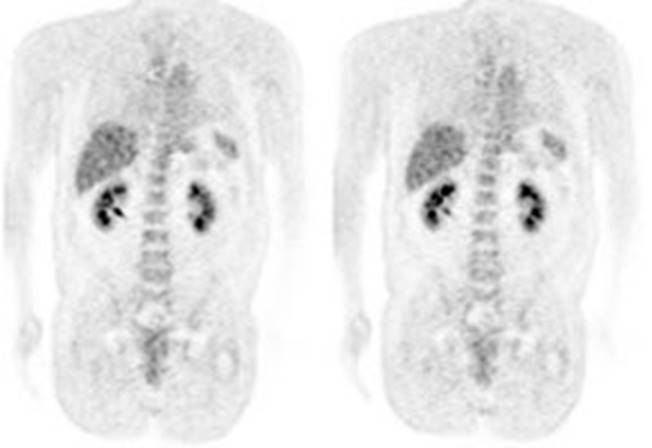

Figure 4 - Myocardial activity: Myocardial uptake can be

very variable. The patient on the left below had a glucose level of 97 prior to

FDG injection. Despite the normal serum glucose, note the intense cardiac

activity in this patient. The patient on the right